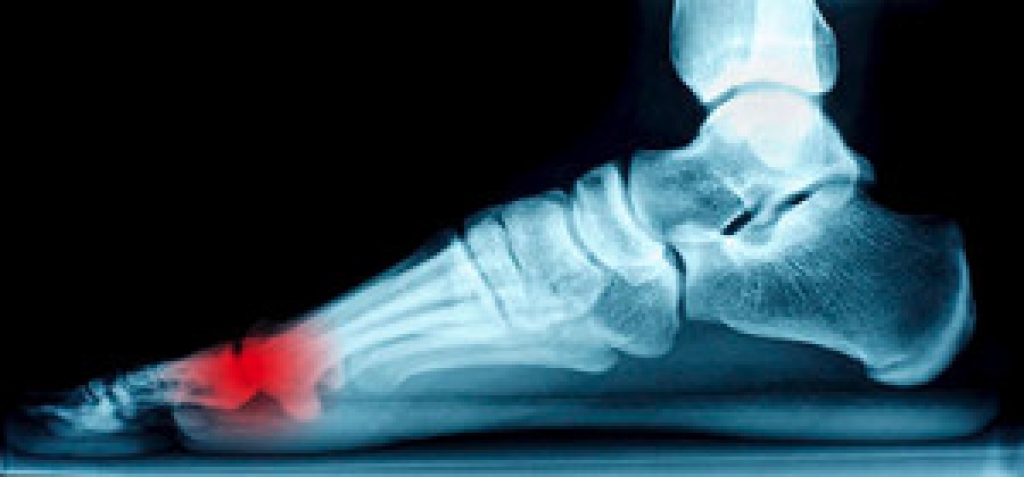

Hammertoe is a foot deformity that affects the joints of the second, third, fourth, or fifth toes of your feet. It is a painful foot condition in which these toes curl and arch up, which can often lead to pain when wearing footwear.

Orthotics – Custom made inserts can be used to help relieve pressure placed on the toes and therefore relieve some of the pain associated with it